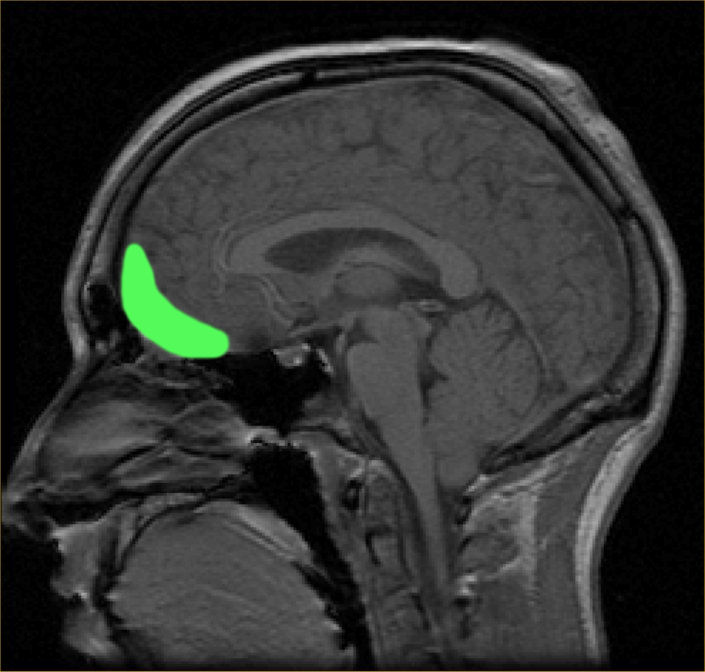

[7] The prefrontal cortex

The main functions of the orbital frontal cortex (the ventromedial region of the frontal lobe), the lower surface of the frontal lobe, just behind the eyes,

The frontal cortex is involved in executive control, delayed gratification, long-term planning. The frontal lobes are connected to every other part of the human. Thus, when the frontal lobes get the right input from other parts, they produce the right output.

prefrontal cortex, which is the closest to the forehead, is the center for concentration, logic, creativity, inhibition, delayed gratification, planning, judgment, execution, and expression (Sapolsky, 2005; Allman, 2000).

The prefrontal cortex (Al-Nasiya):

The orbital frontal cortex (the ventromedial region of the frontal lobe), is located in the lower surface of the frontal lobe, just behind the eyes,

The frontal cortex is involved in executive control, delayed gratification, long-term planning. The frontal lobes are connected to every other part of the human brain. Thus, when the frontal lobes get the right input from other parts, they produce the right output.

The prefrontal cortex (nasiya), which is the closest to the forehead, is the center for concentration, logic, creativity, inhibition, delayed gratification, planning, judgment, execution, and expression (Sapolsky, 2005; Allman, 2000).

MRI of orbitofrontal cortex, By Paul Wicks (2003) The brain-basic and limbic system